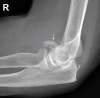

Lateral view 사진에서 골편을 확인합니다.

대부분의 골편은 소두의 본체에서 전방 및 근위부에 위치합니다.

골편이 작은 Type 2는 진단이 어렵습니다.

X-ray : 소두 골절(Capitellum fracture)